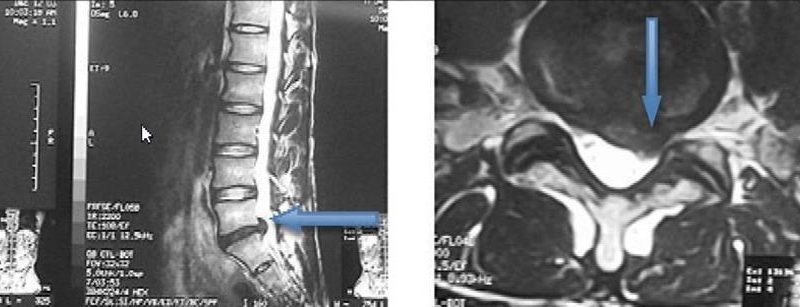

O que é a neuroestimulação? A neuroestimulação é uma técnica médica que utiliza impulsos elétricos de baixa intensidade para modular a atividade do sistema nervoso central e periférico. Ao interferir com os sinais de dor que vão da periferia do nosso corpo para o cérebro, este tratamento oferece um alívio significativo e duradouro para muitas […]